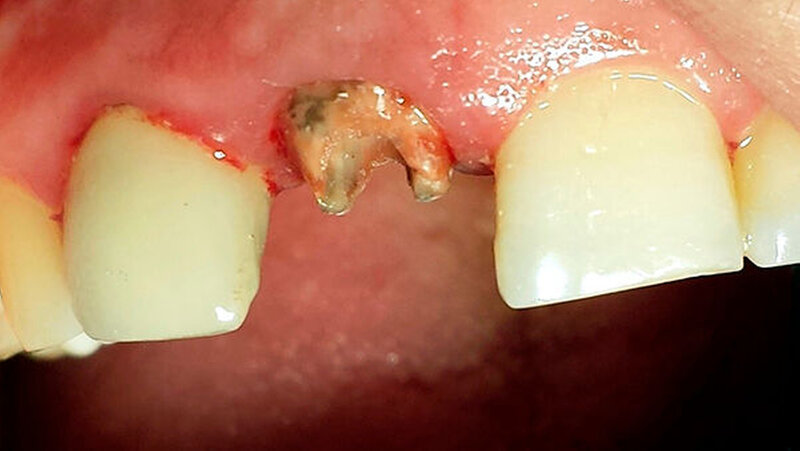

Ein 28-jähriger Mann stellte sich Ende Juli 2015 in der Poliklinik der Universitätszahnklinik Mainz mit herausgefallener Krone an 11 vor (Abbildung 1). Der Patient äußerte den Wunsch der Kronenneuversorgung an 11 und 21 - bei weitestgehend freiliegender Präparationsgrenze mit starker ästhetischer Einschränkung.

Im Verlauf der Behandlung wurden die prothetische Suprakonstruktion an 11 abgenommen und der Zahn retrepaniert. Durchgeführt wurden eine Revision der weitestgehend insuffizienten und überfüllten Wurzelkanalfüllung sowie eine zweiwöchige Kanaldesinfektion mit Kalziumhydroxid. Im apikalen Bereich wurde anschließend nach ausreichender manueller Aufbereitung in Circumferential Filing Technik sowie chemischer Desinfektion ein apikaler MTA-Plug (Mineral Trioxid Aggregat) eingebracht (Abbildung 3) und kondensiert. Es erfolgte eine röntgenologische Kontrolle des apikalen Verschlusses (Abbildung 4). Der Kanal wurde dann erneut provisorisch mit einer Kalziumhydroxidpaste versorgt und der Zahn mit Cavit verschlossen. Die Krone wurde mit Temp Bond rezementiert.